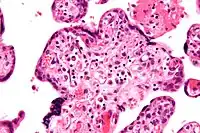

Histopatología

Histomorfológicamente, la VUE se caracteriza por un infiltrado linfocitario de las vellosidades coriónicas sin una causa demostrable. Las células plasmáticas deben estar ausentes; la presencia de células plasmáticas sugiere una etiología infecciosa, por ejemplo, infección por CMV.

La VUE puede ser de 2 tipos, villitis crónica de bajo grado o villitis crónica de alto grado. La vellosidad crónica de bajo grado involucra menos de 10 vellosidades que contienen linfocitos. La vilitis crónica de bajo grado puede ser focal o multifocal. Focal ha involucrado vellosidades en solo un portaobjetos de vidrio, mientras que multifocal ha involucrado vellosidades en al menos dos portaobjetos. La vellosidad crónica de alto grado tiene más de 10 vellosidades inflamadas por foco. La villitis crónica de alto grado se diferencia en difusa y parcheada. El término parcheado se usa si menos del 30% de las vellosidades distales están involucradas. El término difusa se utiliza si más del 30% de las vellosidades distales están involucradas.